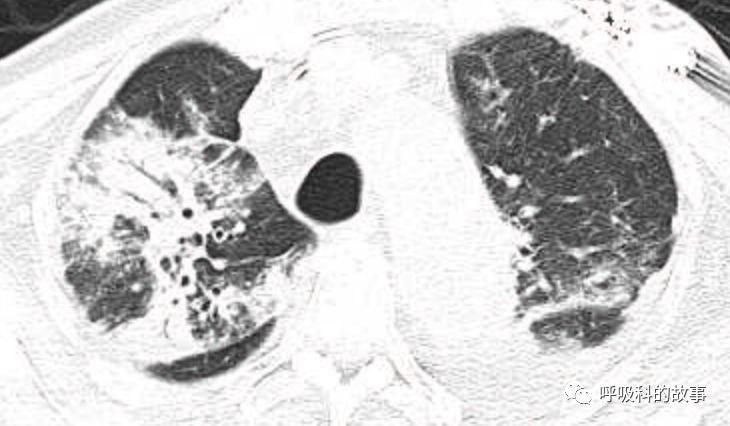

肺部CT如下:

以上的CT给我第一眼的感觉是肺炎,再结合患者有发热和血炎症指标明显增高,肺炎的诊断应该没有问题,但是胸水又是漏出液,结合脑钠肽增高和患者有胸闷气急的症状,心功能不全的诊断也能成立。在某些层面,肺部实变影以内中带为主,还要考虑肺水肿的诊断。入院后给予患者美罗培南抗感染、托拉塞米利尿治疗,以及化痰、雾化处理,患者体温在入院后三天就正常了,入院第五天复查NT-proBNP3390pg/ml;血常规示白细胞 13.5*10^9/L,中性粒细胞81.8%,淋巴细胞13.2%,超敏C-反应蛋白 25mg/L;电解质示钠 160mmol/L,氯 111mmol/L 。虽然炎症指标和心功能指标均有好转,但患者却仍旧精神差,每次查房时仍然表现嗜睡状,家属也反映患者不论白天还是夜晚多数时间不是太清醒。那么问题出在哪里呢?